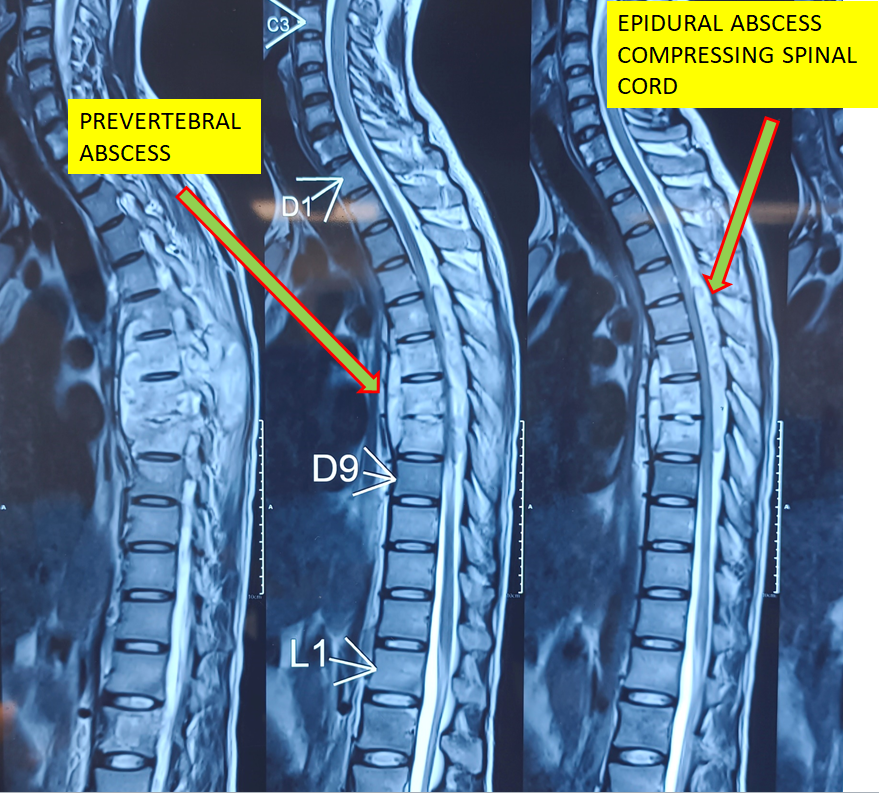

TB SPINE / TUBERCULOSIS IN SPINE / KOCH DISEASE / INFECTION IN SPINE – COMPLAINTS :- A PATIENT CAME ON WHEEL CHAIR WITH COMPLAINTS OF UNABLE TO STAND OR WALK WITH SEVERE UPPER BACK PAIN WITH SIGNIFICANT WEIGHT LOSS IN LAST 1-2 MONTHS. DIAGNOSIS :- VERTEBRAL END PLATE DAMAGE WITH EPIDURAL ABSCESS WITH SEVERE COMPRESSION OF SPINAL CORD. SURGERY :- SPINAL FIXATION SURGERY WITH TITANIUM SCREWS AND RODS WITH SPINAL CORD DECOMPRESSION WITH EPIDURAL ABSCESS DRAINAGE AND BIOPSY OF DEAD TISSUE AND SAMPLE IS SENT TO LABORATORY FOR EXAMINATION. RECOVERY :-THE PATIENT STARTED SITTING FROM DAY 1 AFTER THE SURGERY. HE STARTED WALKING WITH SUPPORT FROM 2 ND DAY AFTER OPERATION. AFTER REGULAR EXERCISES AND PHYSIOTHERAPY NOW HE CAN WALK AND SIT PAIN FREE. ON BIOPSY REPORT TUBERCULOSIS INFECTION IS DIAGNOSED, SO WE STARTED MEDICINE FOR TB FOR 1 YEAR.